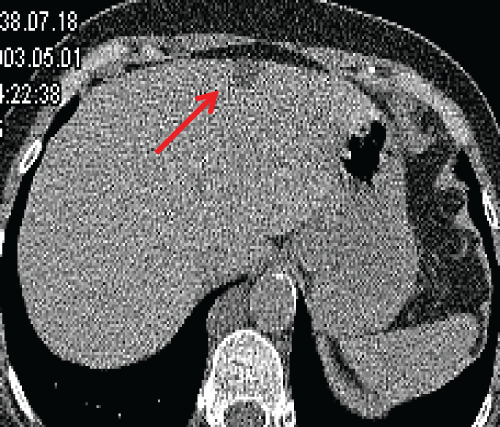

One hundred and thirty four (8.5%) exhibited findings of little or no clinical significance (category 1) for prevalence of 8.5 %. There was no change in size or attenuation of findings in any subject in category 1 on two subsequent annual screening CT scans. Incidental CT findings of variable clinical significance (category 2) were demonstrated in 44 out of 1572 subjects for prevalence rate of 2.8 %. One anterior mediastinal nodule increased in size and two cases of thyroid hypodensities were lost to follow-up in category 2. The findings in the remaining 41 did not change over two subsequent annual CT scans. The majority of incidental findings in category 1 and 2 were stable over a two year period (Figure 1, Figure 2 and Figure 3).

Figure 1: 57-year old woman with a simple hepatic cyst. Axial LDCT image shows a simple appearing cyst (arrow), however given noisy images, a follow-up ultrasound (not shown) was performed to confirm.